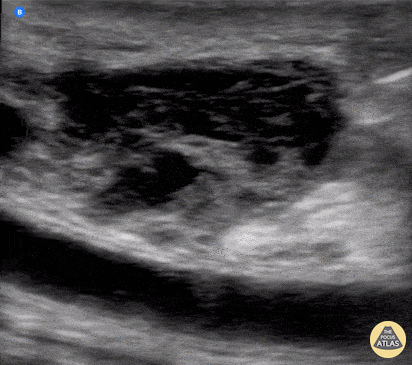

Needle aspiration of a fluid collection superficial to a femoropopliteal bypass. Wolfgang Geisser, @fentanyl05 Bayern, Deutschland